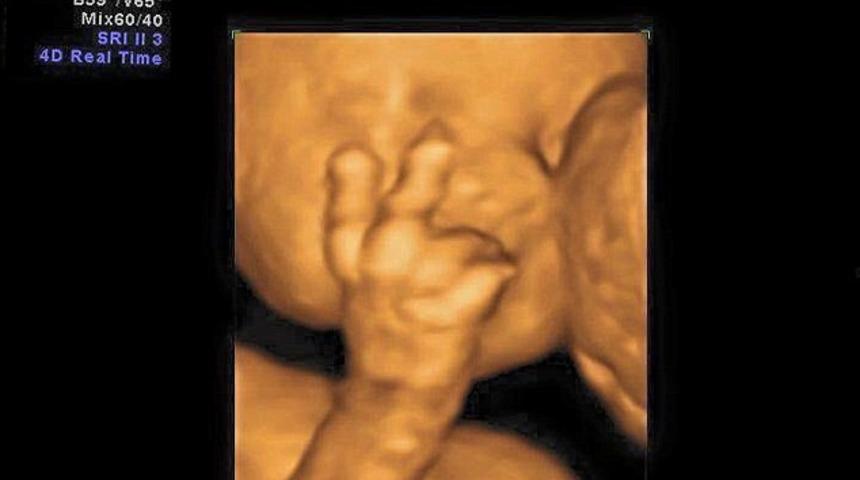

4 boyutlu teknoloji kullanılarak yapılan taramalar inanılmaz anları ortaya çıkarabiliyor.

Bebek Edward Kasım 2015 doğumlu. 2015'in Eylül ayında 7 aylık tarama sırasındaki ultrason görüntülerinde kimi zaman gülüyor, esniyor, kimi zaman derin düşüncelere dalmış gibi...

4D taramalarda anne babalar çocuklarının nasıl görünecekleri merak ettikleri için artık daha da popüler hale geldi.

Gebelik süresince 3 veya 4 boyutlu ultrason yapılması rutin olarak şart değildir, bu sadece aile bebeğin yüzünü, ellerini v.b görmek isterse faydalıdır, bebeğin durumunu ve özür varlığını araştırmakta faydalı değildir. Gebelikte rutin olarak normal 2 boyutlu ultrasonların kullanılması yeterlidir.